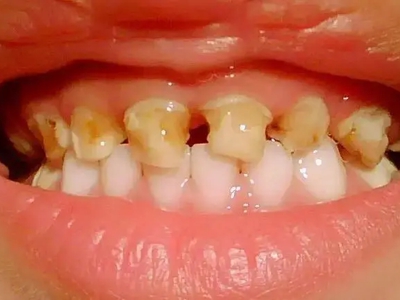

牙釉质发育不全牙齿棕色有缺损图

牙釉质发育不全患者牙齿出现明显的缺损表现,并于表面形成深褐色的蜂窝状、竖条状的凹坑,甚至形成洞,患者上下牙失去咬合能力。